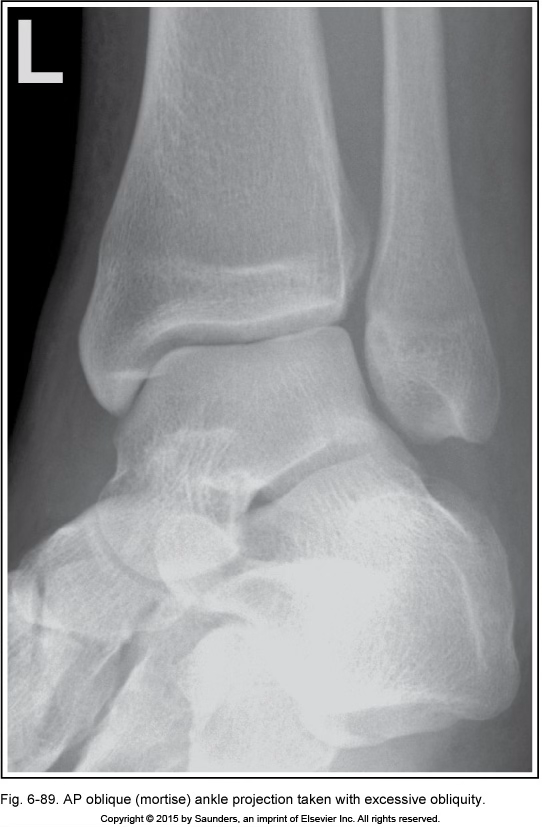

AP ankle oblique (mortise)

excessive obliquity

too much joint space